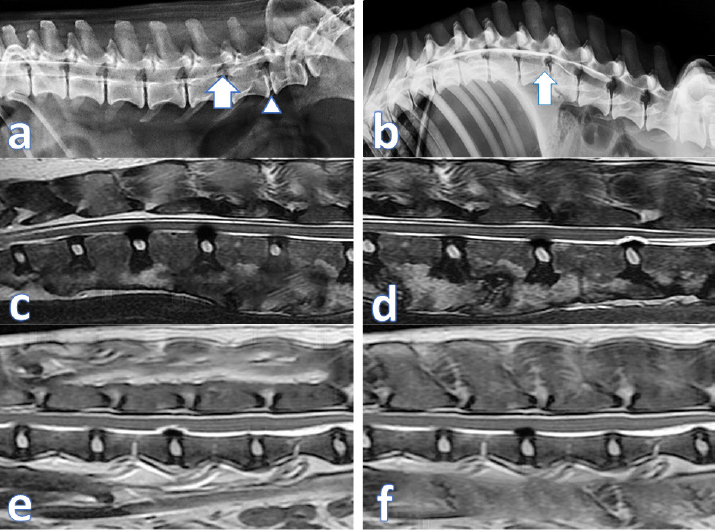

All animals in this study showed major clinical improvement starting from 15 days post injection with physical rehabilitation at home, restored the control over the urination in all animals mostly from the second week post transplantation (Supplementary video showing the clinical improvement of case 1: https://www.openveterinaryjournal.com/case-1), regained the reflexes tone, and regained control of the full weight bearing locomotion without assistance around 60 days post transplantation for dogs and 45 days post transplantation for cats (Figs. 13). Magnetic resonance did not show a marked improvement over the 90 days for the intervertebral disc extrusion lesions (Fig. 4).

The other part of the cells was applied intravenously to obtain full coverage of the lesion to reach the spinal cord or the damaged peripheral nerves too (Akiyama et al., 2002; Kim et al., 2015). The systemic application of cells was safe and did not produce any adverse reactions or complications as stated in the previous studies. The MRI scans did not show a major improvement regarding the protruded discs. This might be attributed to the longer periods required for intervertebral discs to heal (Skovrlj et al., 2015). However, the clinical signs were ameliorated due to the transplanted SCs capable of stopping the inflammation, necrosis, and apoptosis and stimulating the regeneration of the neurons and axons (Kim et al., 2015). This combination proved its safety as no adverse effects were recorded in all animals included in this study from the surgery day till 90 days post-transplantation.

Fig. 4. (a) contrast Myelography where spinal cord of a cat 1 showing mild degree of spinal cord compression (arrow) and severe disc compression and mineralization (arrow head); (b) spinal cord myelography of a dog 1 showing severe compression (arrow); (c) MRI scan of cat 2 showing the protrusion of 2 discs before treatment; (d) MRI scan of Dog 2 showing the same lesion after treatment; (e) MRI scan of cat 2 showing the disc protrusion before treatment; (f) MRI scan of cat 2 showing the same lesion after treatment.